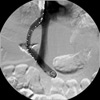

After catheterizing the hepatic vein (draining vein), carbon dioxide is injected demonstrating the location of the portal vein.